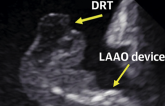

Predictors of Device-Related Thrombus Following LAA Occlusion